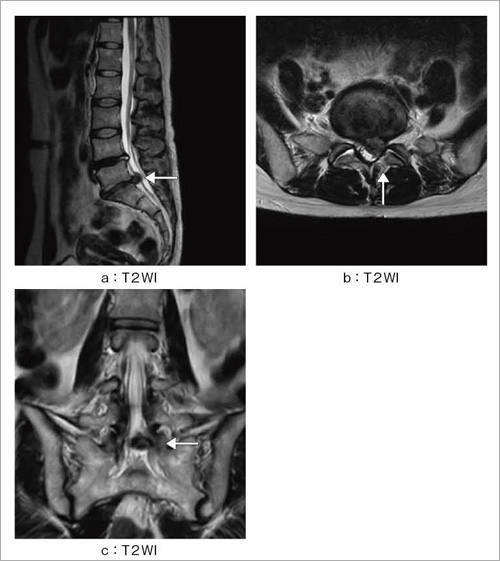

初学者のためのMRIの読み方 | 高橋睦正 |本 | 通販 | Amazon